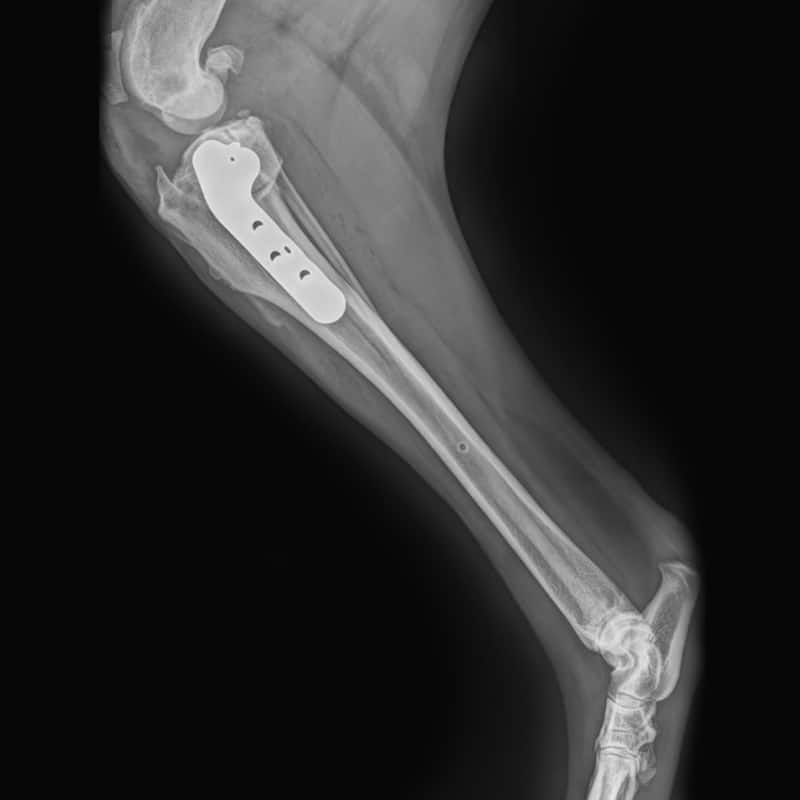

Femoral Head Osteotomies

Surgically removing the head and neck of the femur to alleviate pain and improve mobility in pets who suffer from severe hip joint disease.